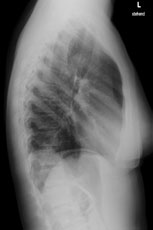

Eine 36-jährige Patientin kommt zu Ihnen in die Praxis. Sie berichtet über einen grippalen, fieberhaften Infekt, seit einer Woche bestehend.

In der Lungenauskultation sind Rasselgeräusche beidseits basal zu hören. Bei einem CRP von 160 mg/l veranlassen Sie ein Thoraxröntgen mit der Frage nach Infiltrat.

Hier sehen Sie die Bilder:

Thorax seitlich

Wie lautet Ihre Diagnose?